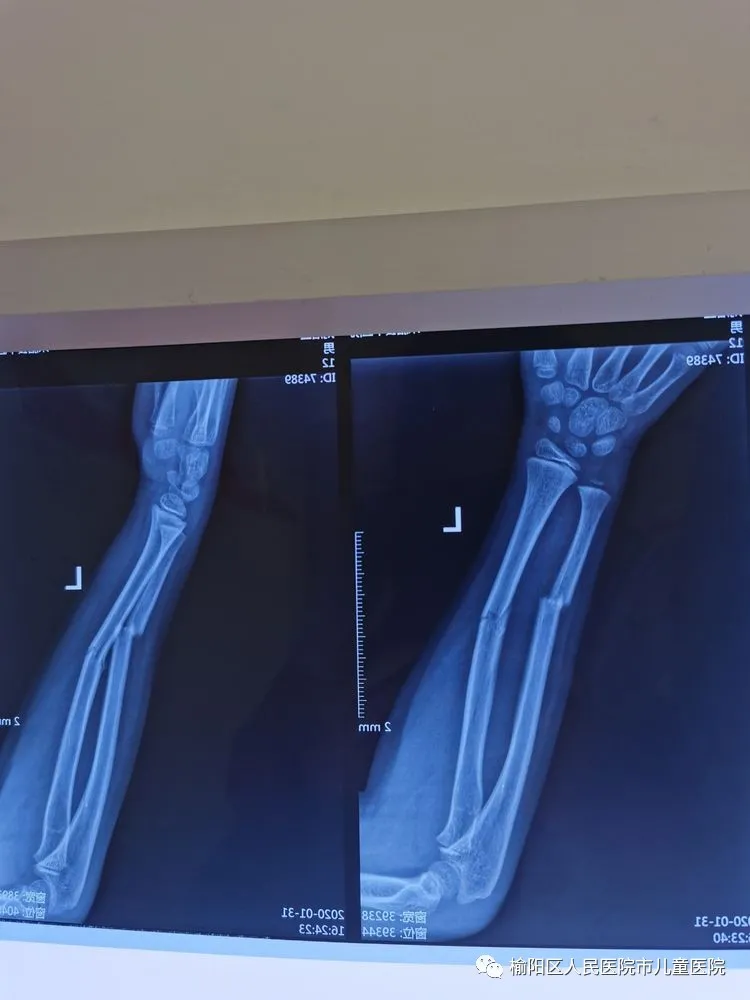

在全麻下行弹性髄内针微创闭合治疗

0.5cm的微创小口

术后5个月,完美愈合。